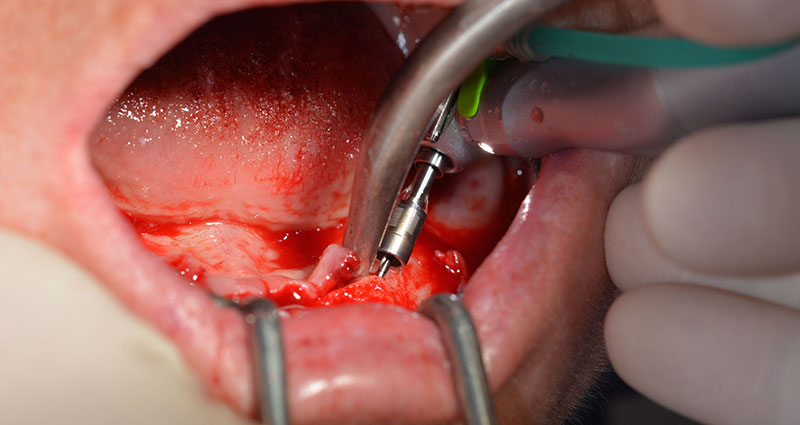

A three-dimensional cone beam computed tomography scan (CBCT, Planmeca) was performed to aid planning and minimize risks. This revealed that the quality and quantity of the available bone were sufficient for the surgery and immediate restoration using the Fast & Fixed method. Following the protocol for this concept, the implants are inserted at 35, 32, 42 and 45. Angling the distal implants by up to 45° shifts the emergence profile to posterior and generates a larger support polygon (Fig. 3).

Fast & Fixed method

Fig. 3